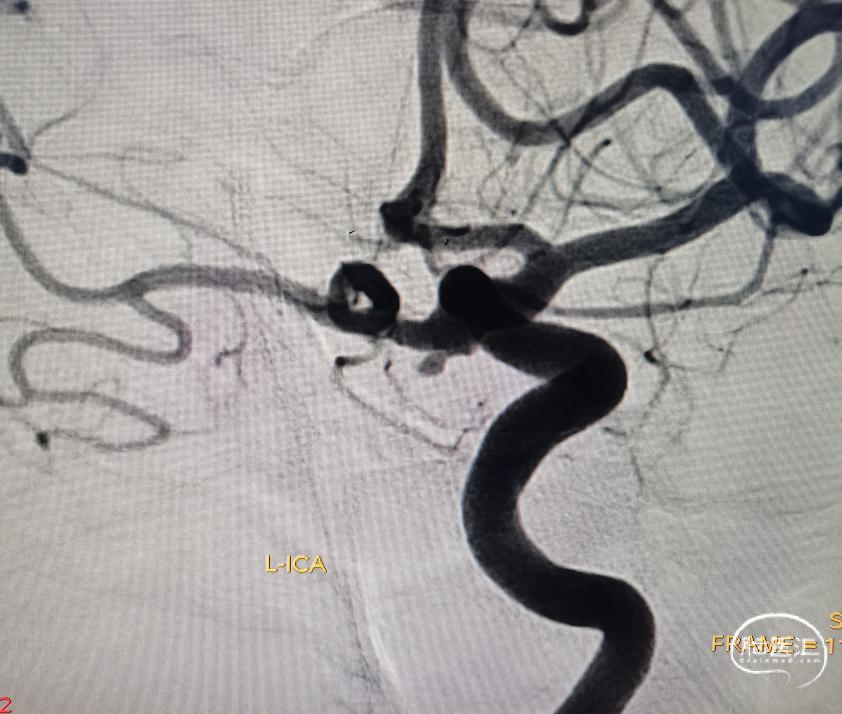

怀疑:左侧后交通的动脉瘤。又上一张CTA。

简单看看,还行。患者辗转到位,还是先安排一下造影吧。于是直接造影。原来跟我们评估的差不多,还是左侧后交通动脉瘤。

正如先前提到,瘤不大,需要精准微导管塑型。胚胎大脑后动脉,因此,载瘤动脉还是需要保的。于是乎,左选选,右选选。到底选啥支架那?利用弹簧圈微导管输送的支架,没货。所以只有选择普通支架输送的微导管。因此问题来了,如果用普通的支架微导管,直径比较粗,因此当进入后交通动脉时,导管张力特别大,有顶破动脉瘤的风险。所以,没有可选,直接微导管交换三米支撑导丝,把支架导管输送上去。